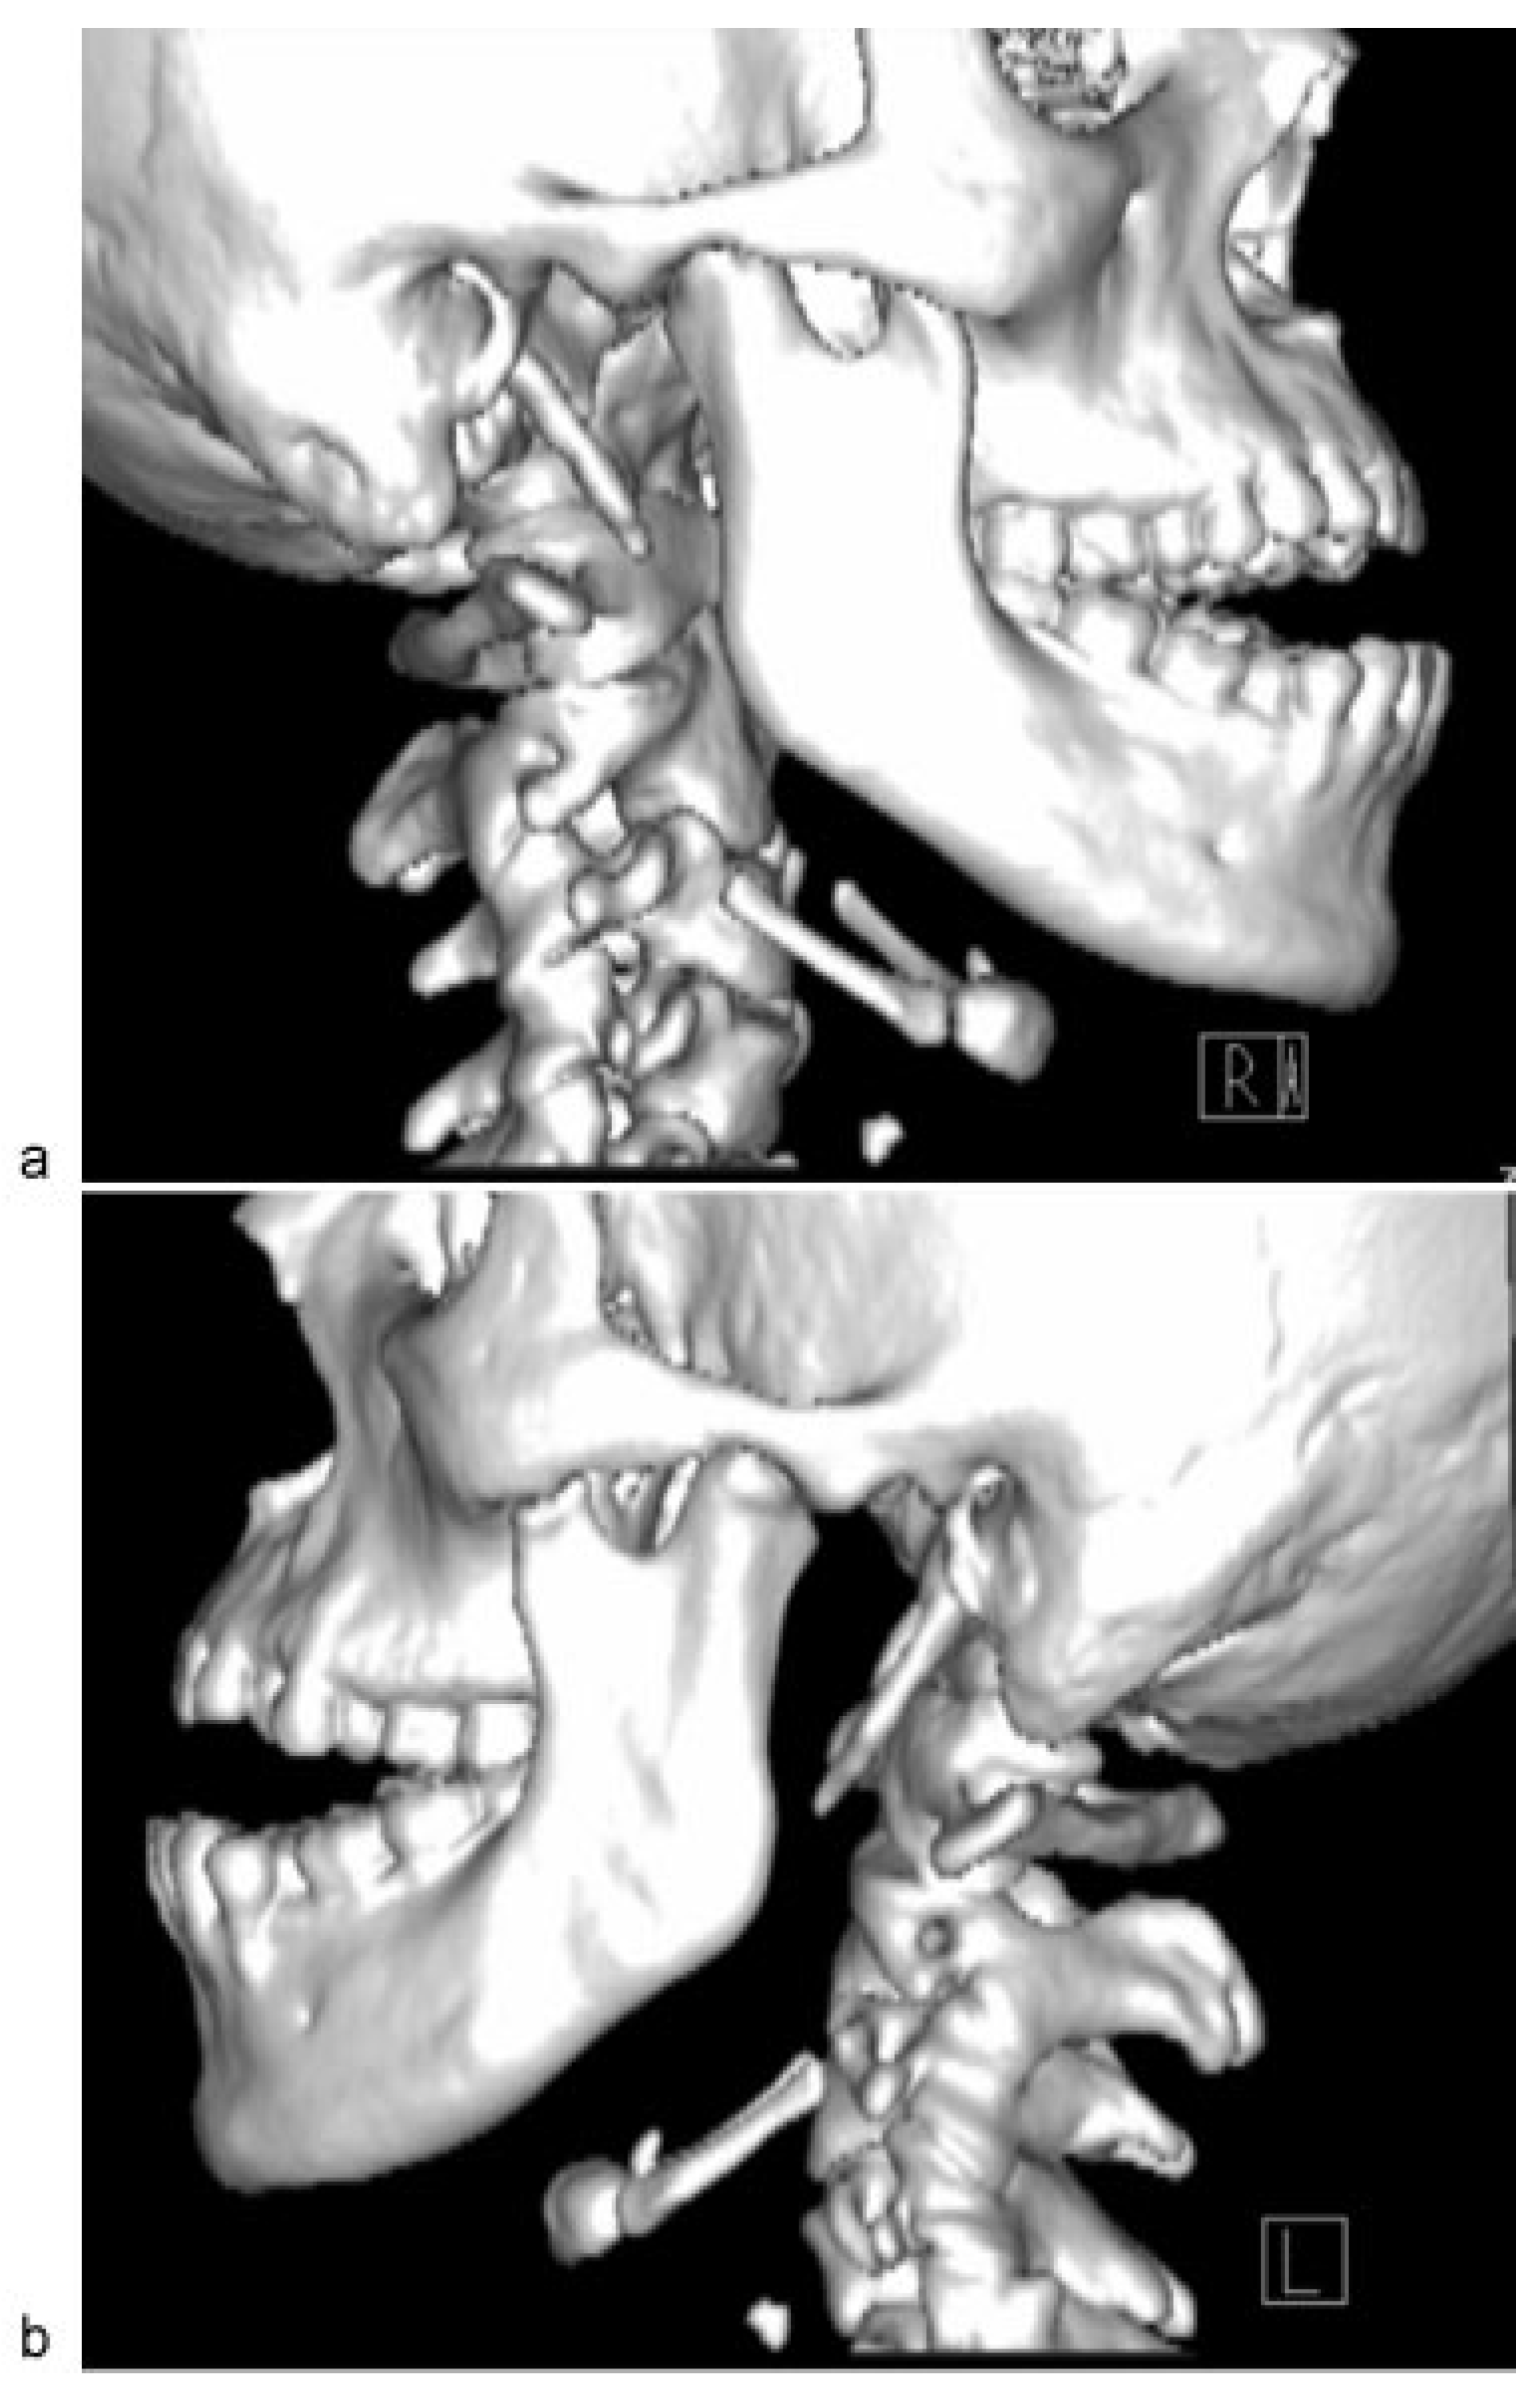

Examination revealed maximum mouth opening was 42 mm with 15 mm of anterior open bite upon closing. Computed tomographic (CT) scan that was taken immediately post-MVA shows no fractures to his facial skeleton and both condylar heads were located in the glenoid fossae ([Figure 1]). He was subsequently sent for another CT scan to view the position of the condyles. Both condylar heads of the mandible were anteriorly dislocated from the TMJ fossae and were located at bilateral infratemporal fossae ([Figure 2]). Closed reduction of the TMJ was attempted for a few times; however, it was unsuccessful because of the stiffness of muscle of mastication.

Figure 2. Dislocations of right and left condylar heads into infratemporal fossa.